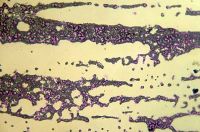

Pancytopenie. Změny v počtu krevních elementů tvořících se v kostní dřeni se rozvíjí nejdříve po 24 hodinách od ozáření. Úbytek buněk souvisí s počtem buněk dané linie v kostní dřeni a mírou úhynu. Destruované buňky z kostní dřeně mizí a jsou nahrazovány částečně lipocyty. Pokles buněčnosti kostní dřeně je doprovázen dilatací sinusoidů, což má za následek časné krevní extravasáty, které jsou podobné skutečným hemorragiím. V případě leukocytů je změna výrazná, kdežto u erytrocytů se i u úplného zastavení produkce nových buněk v kostní dřeni projeví poklesem populace o 0,8 % denně. Navíc, expozice organizmu dávkám ionizujícího záření se manifestuje úbytkem nezralých forem krvetvorných buněk, kdežto formy diferencovanější bývají kvantitativně nedotčeny a dále vyzrávají a jsou i po ozáření uvolňovány do krevního oběhu. Změny v krevním obraze se tudíž manifestují až po dozrání zachovaných diferencovanějších stádií krevních elementů, v čase, kdy hypoplastická až aplastická kostní dřeň není schopna uvolnit do krevního oběhu další zralé buňky. Proto jednotlivé krevní elementy mizí z periférie v závislosti na délce života.

Lymfocyt. Kostní dřeň má značnou regenerační schopnost a i při dávkách přesahujících hodnotu 6 Gy přetrvávají ostrůvky schopné regenerace. Některá ložiska mohou být pouze abortivní, jiná právě postupně regenerují. V důsledku poškození chromozomů je možné pozorovat i četné abnormální mitózy a chromozómové aberace, z nichž některé mohou přetrvávat i řadu let. Jedná se především o výskyt chromatinových můstků, mikrojader, multioilárních mitóz a vznik obrovských buněk.